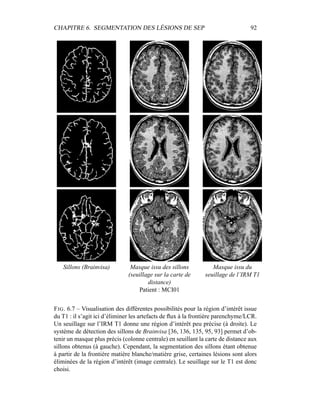

1

N

i=1

γk

i

µk =